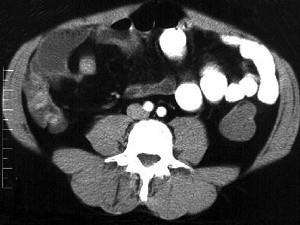

问题 女,30岁,右下腹痛,腹泻便秘交替出现,消瘦乏力,血沉加快,X线检查如图,最佳的诊断是 ( )

选项 A、结肠癌 B、阑尾炎 C、小肠结核 D、小肠克罗恩病 E、小肠癌

答案 D